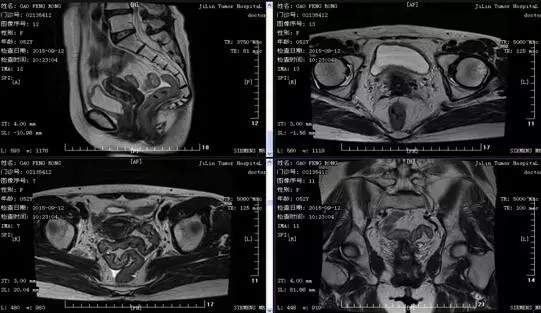

放疗后1个月2015-9-12复查盆腔MRI:子宫颈略增大,壁略增厚,未见确切肿块信号影,周围脂肪间隙见索条影,盆腔内未见明显肿大淋巴结。1.子宫颈癌放化疗后,子宫颈略厚,较2015-7-17影像片肿块基本消失。